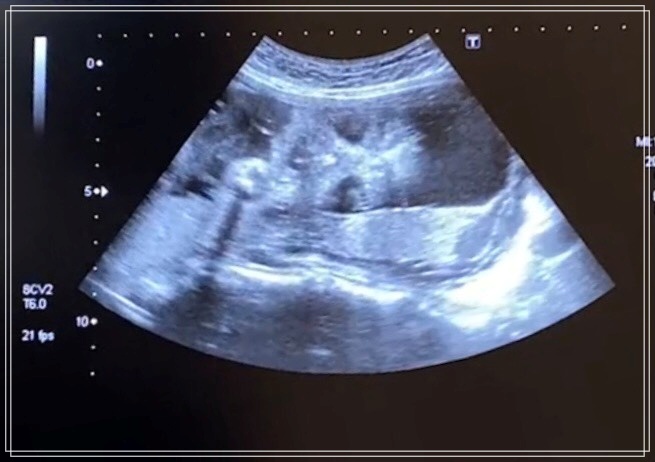

チビきっきんは相変わらずの逆子状態で、元気に動いてました。

元気に動いてくれてるときはお腹を触っていなくてもわかるほどでした。

一般的に、この時期になると個人差はありますが体長は35cm〜38cm、体重は750〜1100g程度になります。

カラダの器官もほぼ完成され、視覚・聴覚・味覚も発達し、情報を脳に伝達する機能も完成してきます。

この時期から、「肺呼吸」が始まり羊水を吸い込んだり、吐いたりと呼吸の練習を始めます。